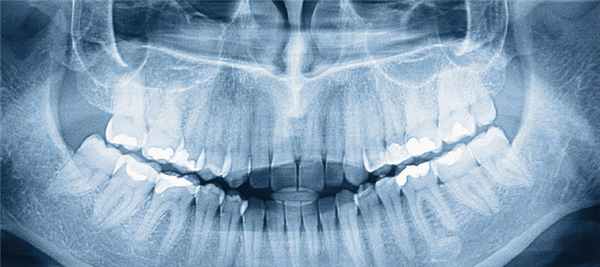

Ортопантомограмма (ОПТГ)

Это один видов исследования, пользующийся достаточным спросом. С помощью данной методики удается получить изображение абсолютно всех челюстей и зубов.

Что дает панорамный снимок зубов?

Полученное изображение дает специалисту следующие сведения:

- Наличие фибром и других новообразований.

- Скрытый кариес.

- Выявить непрорезавшиеся зубы и их точное положение.

- Выявить костные заболевания.

Другими показаниями к ОПТГ являются предстоящая процедура имплантации, запланированное хирургическое вмешательство, а также другие сложные манипуляции.

Панорамный

Если вам назначили рентген одновременно всех зубов, то у многих может возникнуть вопрос – как называется эта процедура? Здесь подразумевается панорамный снимок, который делается с помощью ортопантомограммы.

Перед исследованием голову пациента необходимо надежно зафиксировать, ведь любое движение может сделать изображение нечетким. После этой подготовки начинается процедура: специальный аппарат совершает обороты вокруг головы (с одной стороны устройства находится пленка, а с другой – трубка).

Если говорить о том, как часто можно делать ортопантомограмму зубов, то в год допустимо до 10 панорамных снимков, а при использовании современного оборудования в разы больше.